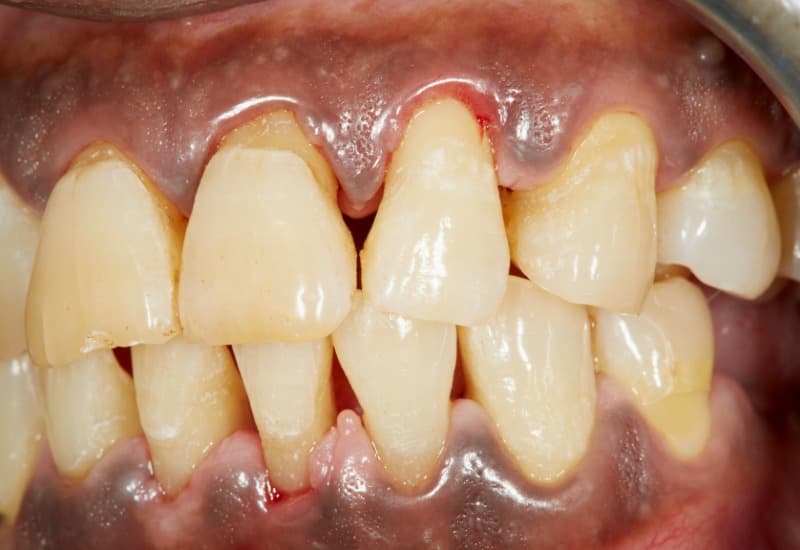

– Mảng bám và cao răng: Mảng bám và cao răng là nguyên nhân phổ biến nhất gây sưng lợi. Mảng bám là lớp vi khuẩn bám trên bề mặt răng, nếu không được vệ sinh thường xuyên, chúng có thể tích tụ thành cao răng. Các răng trong cùng trên cung hàm là các răng khó vệ sinh, dễ tích tụ mảng bám và cao răng nhất. Bởi thế, lợi trong cùng cũng là khu vực dễ sưng nhất.

Mảng bám là lớp vi khuẩn bám trên bề mặt răng, chúng có thể tích tụ thành cao răng, gây sưng lợi.

– Bệnh lý nha chu: Các bệnh lý nha chu như viêm lợi hoặc viêm nha chu có thể gây sưng, đỏ và đau lợi. Các tình trạng này có thể dẫn đến tổn thương mô lợi và xương hỗ trợ răng.